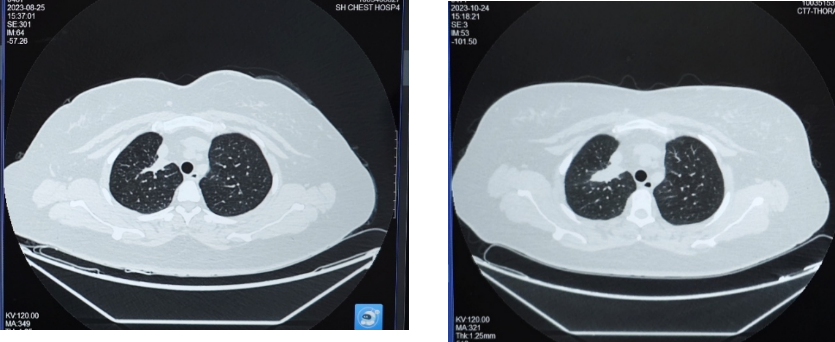

2023年10月24日复查胸部CT,示右肺上叶实性肿块影,大小约37×15mm,与2023年8月25日CT相比病灶增大,评估为靶向治疗耐药导致疾病进展(PD)。

第一阶段:2024年1月19日首次复查,肺部病灶较前缩小,大小约34×11mm;2024年4月22日复查,肺部病灶较老片相仿,疗效评价维持SD,治疗方案调整为“培美曲塞+PD-1单抗+贝伐珠单抗”,并开始使用双膦酸盐进行骨保护治疗。